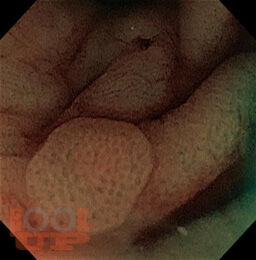

В предлагаемом учебном пособие представлены сведения об этиологии, морфологии и патогенезе эпителиальных образований ЖКТ, методике эндоскопического удаления полипов толстой кишки. Пособие содержит тестовые задания для самоконтроля.

Учебное пособие предназначено для использования при реализации основных профессиональных образовательных программ высшего образования по направлениям подготовки клинических ординаторов 31.08.70 «Эндоскопия», 31.08.67 «Хирургия».